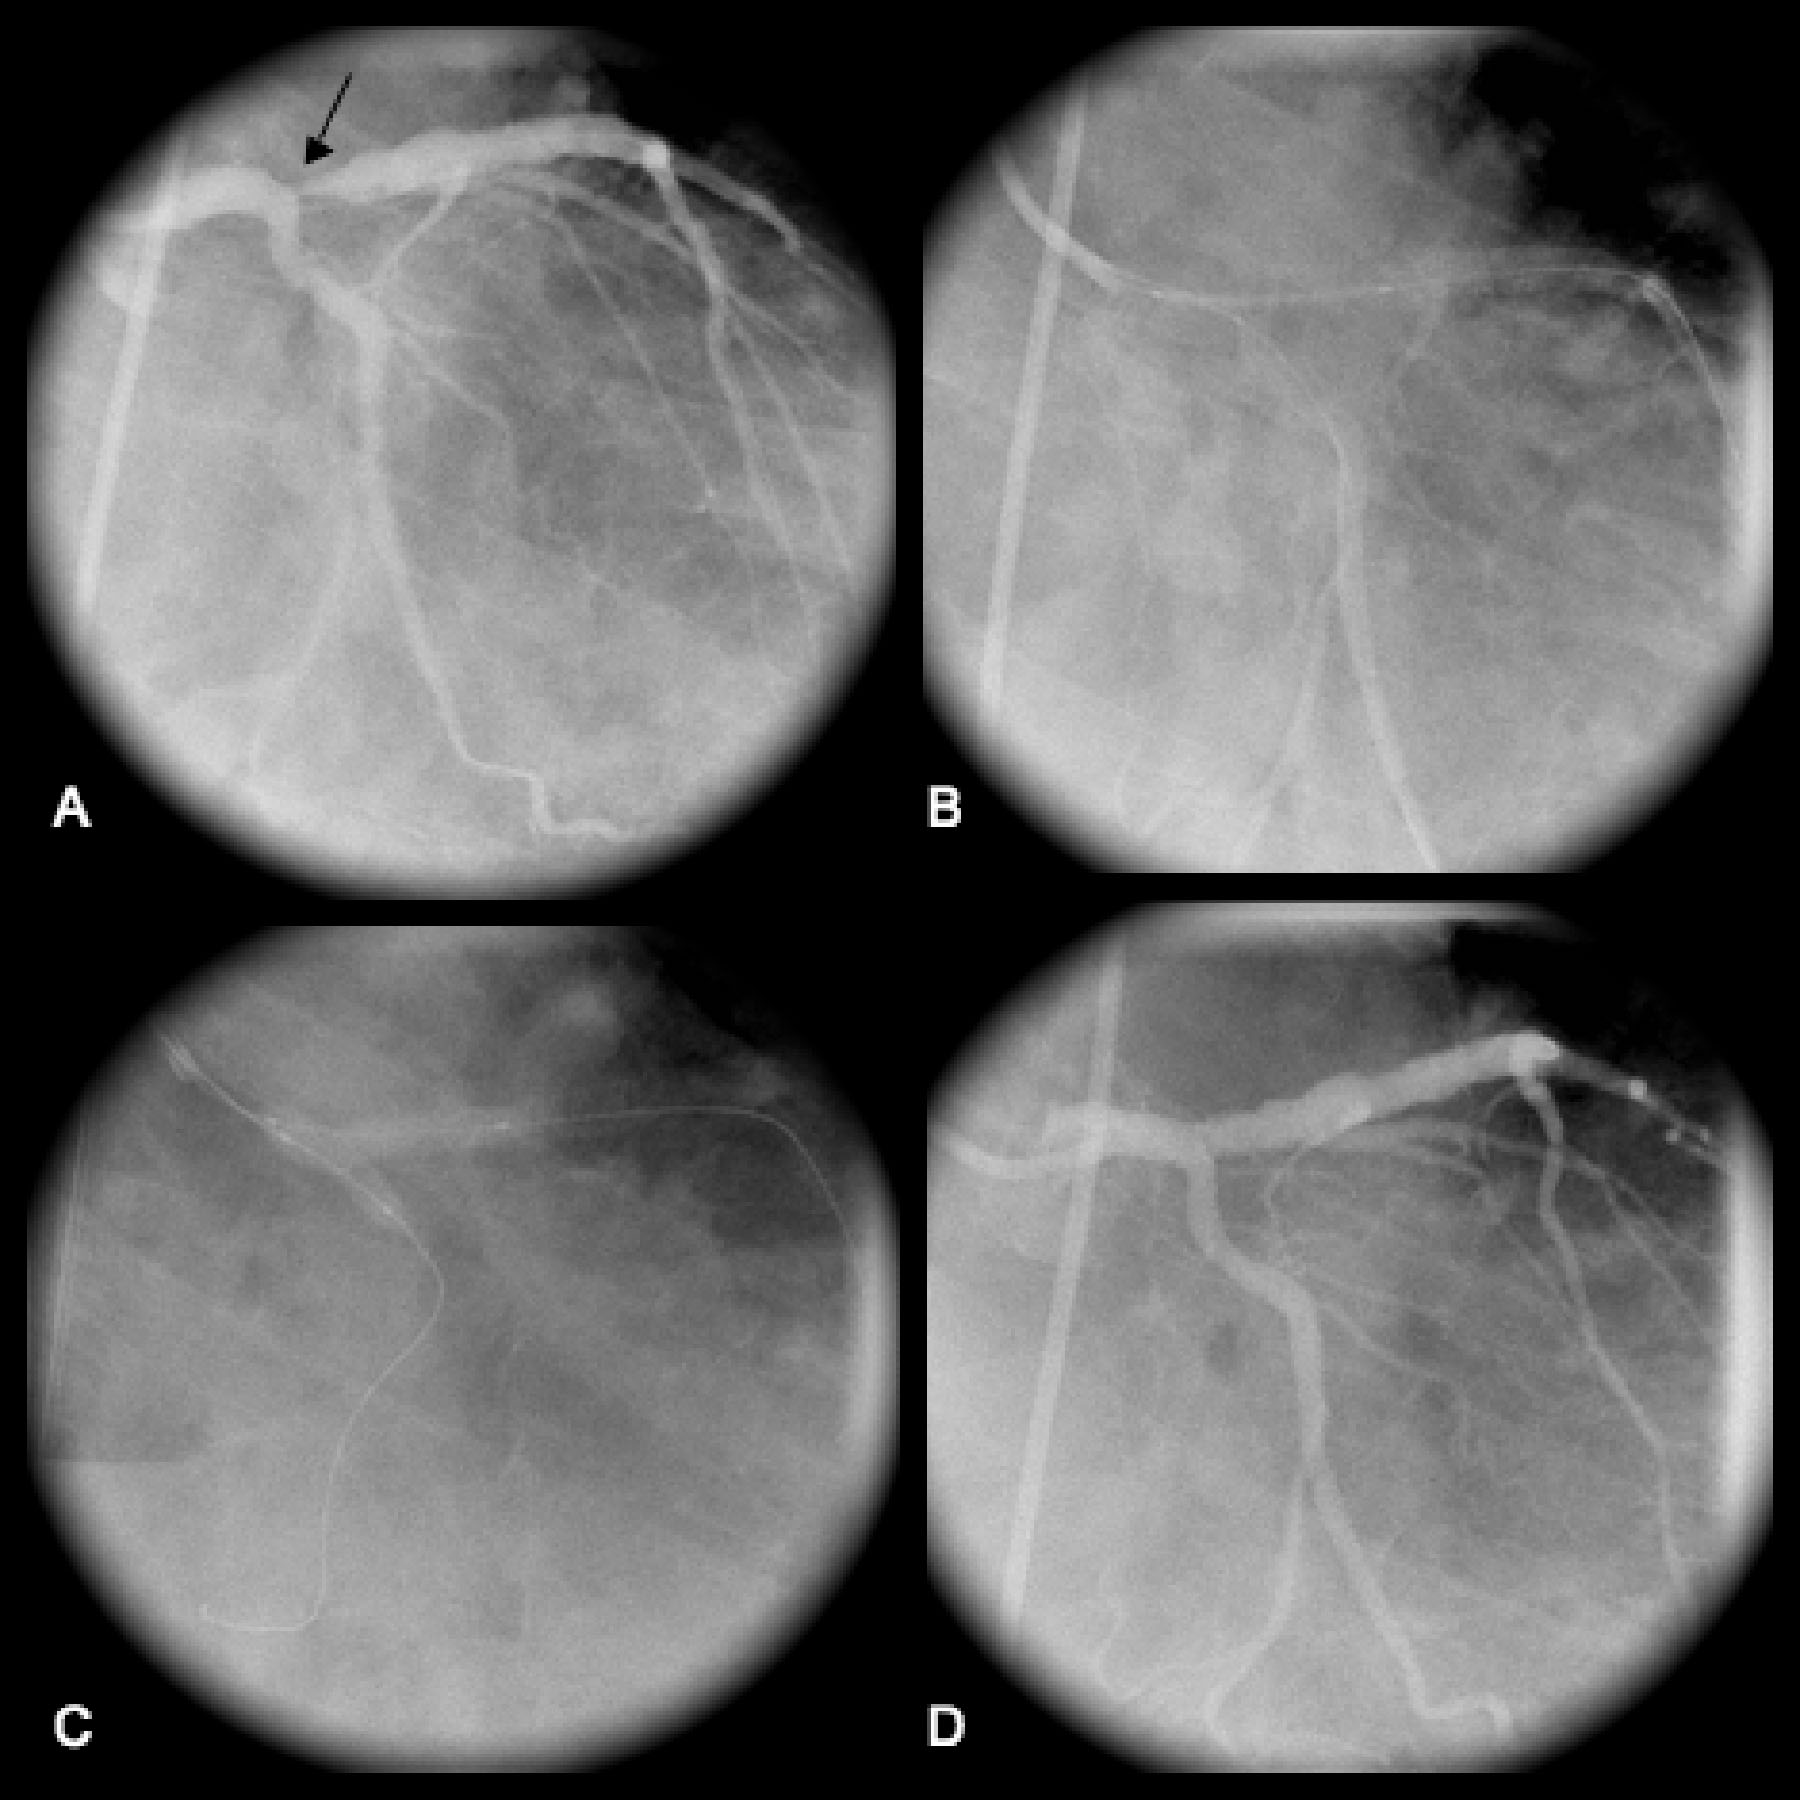

Figure 2 from A Large Isolated Congenital Left Circumflex Artery-to …

Corornary angiogram showing dilated circumflex artery and coronary …

Coronary angiogram: showing left circumflex coronary arteries tumor …

-A) 70%-obstructive lesion of the proximal 1/3 of the circumflex …

A, Right coronary angiogram showed heavily calcified right coronary …

Computed tomography. Huge left circumflex artery to right atrium …